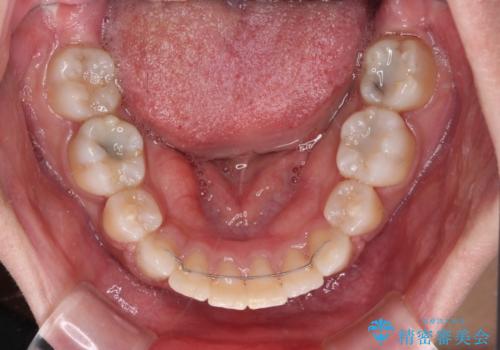

2年ほどインビザラインを使用しましたが、どうしても歯の移動がマウスピースに追随せず、全顎ワイヤー矯正へ切り替えました。

ワイヤー装着後は2年弱で、しっかりと仕上げることができました。